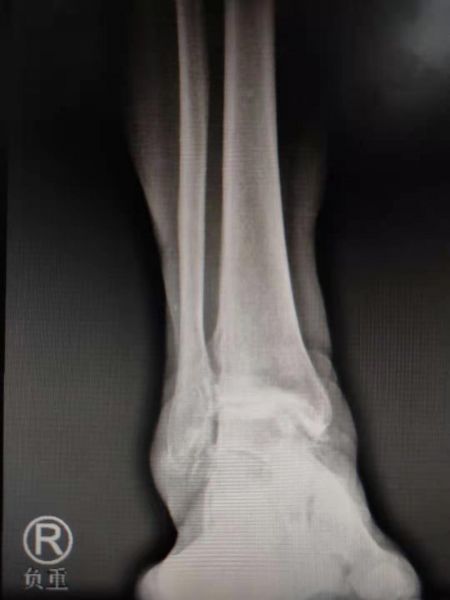

术前X线片

本次接受全踝关节置换术治疗的患者为61岁女性,因“右踝关节肿痛30年余,加重伴活动受限1年”来我院就诊,诊断为右踝关节骨关节炎。北院足踝外科曲文庆主任带领团队经过反复考量,为患者及其家属提供了置换、矫形、融合三种治疗方案。为最大程度地改善患者踝关节功能,提升患者生活质量,通过与患者及家属多次沟通,最终决定进行既能消除疼痛、又能保留踝关节活动度的全踝关节置换术。